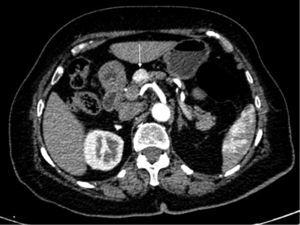

Todos los tumores fueron diagnosticados de forma incidental, con confirmación del diagnóstico mediante TC (fig. 1), RNM o gammagrafía con octreótide. Se realizó ecoendoscopia con punción en 2 pacientes (8%) por dudas diagnósticas, y en ambos se confirmó el diagnóstico de TNP, con bajo grado histológico y un Ki67<5%.